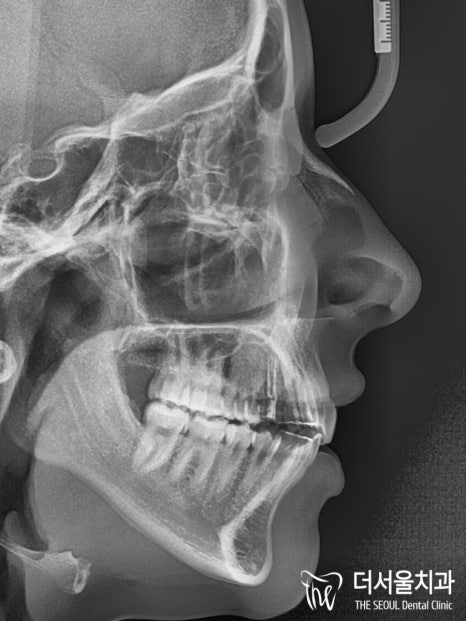

【 초진 】

이분께서는 미국 국적을 갖고 있는 외국인 환자로

첫 번째 치료를 미국에서 진행을 하셨는데요.

음.. 치료를 했던 곳이라는 게 믿을 수 없을 정도로

굉장히 당황스러웠습니다.

마무리가 2급 부정교합으로 되어있더라고요^^..

2급 부정교합 그리고 # 26 크로스 바이트까지

여러 아쉬움이 남는 것으로 확인되었는데요.